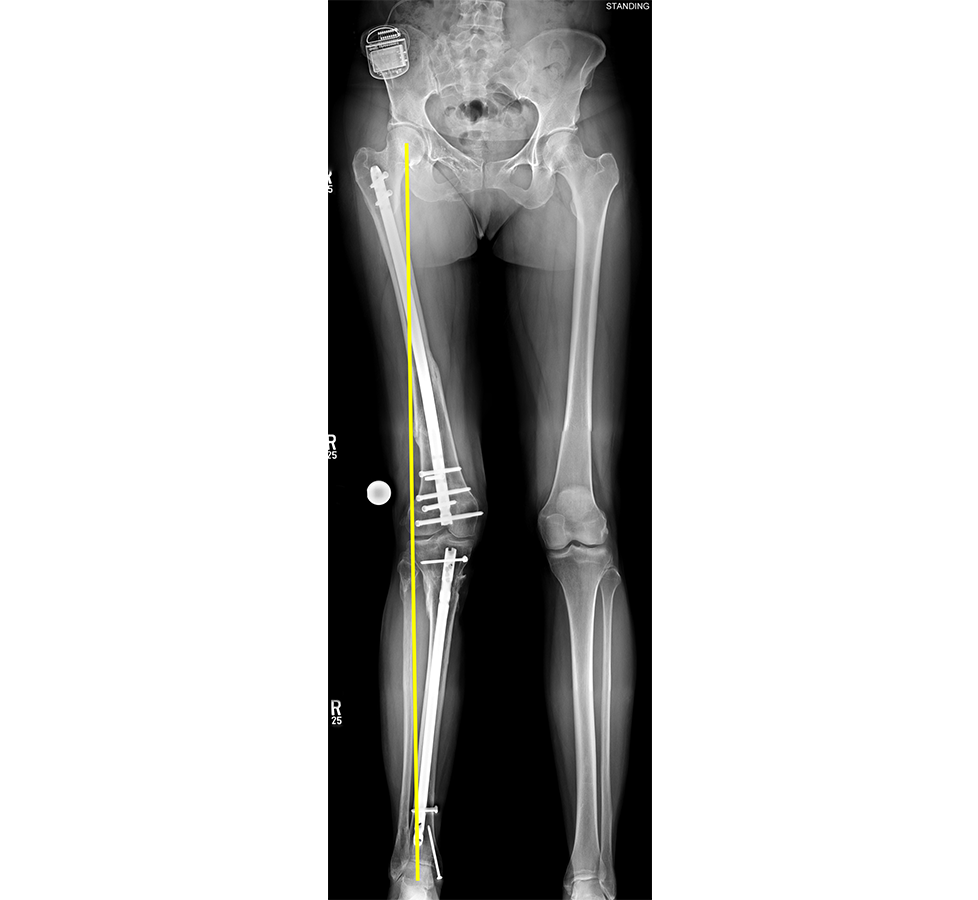

- 47-year-old woman s/p separate femur and tibia trauma

- Valgus knee with external rotation through femur

- Deformity analysis revealed that the angular deformity was coming from her proximal tibia.

The treatment plan was to remove the femoral intramedullary (IM) nail, to perform a derotational osteotomy of the femur with an internal saw, and then to refix the femur with a new antegrade IM nail.

The tibial deformity was planned to be managed with a MAXFRAME AUTOSTRUT™.